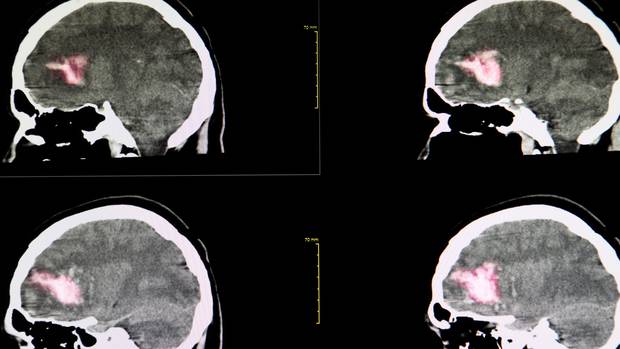

Смртоносен вирус повторно се појави во Кина, инфицирајќи повеќе од 60 луѓе и убивајќи седум.

Високо патогениот, бениген вирус предизвикан од крлеж може да доведе до синдром на тромбоцитопенија.

Тоа предизвикува вирусна хеморагична треска и повторно се појави во руралните области на Кина.